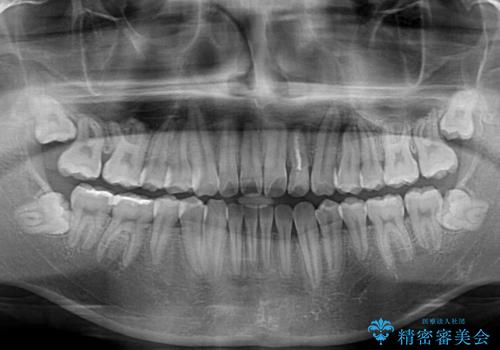

気になっていたクロスバイトは速やかに改善され、1年間で治療を終えることができました。

治療開始前は汚れが多く、全体的に歯肉が腫れていましたが、矯正治療を通して腫れも少しずつ改善されました。